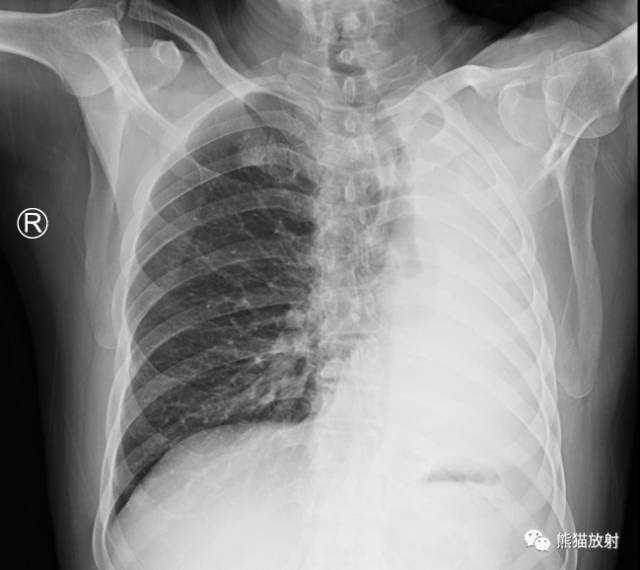

| 一侧性肺气肿 |

(1)过度透明肺可以是单侧或双侧的病变。若是单侧的,它可以侵及全肺、一叶、一段甚至一个小叶。

(4)真正的肺疾病导致单侧过度透明肺是肺血流量减少的反应。其原因包括心脏分流、肺栓塞、肺气肿、支气管内肿块和闭塞性细支气管炎。

(5)X线诊断肺气肿是一个有争论的课题。大多数人同意血管的变化与肺气肿的病理诊断紧密相关。对早期肺气肿的诊断CT较平片敏感。

(7)在大气道阻塞患者,首先决定过度透明侧异常,还是密度增高侧异常。拍摄呼气片、透视或侧卧位片来肯定空气积聚是很容易的事。